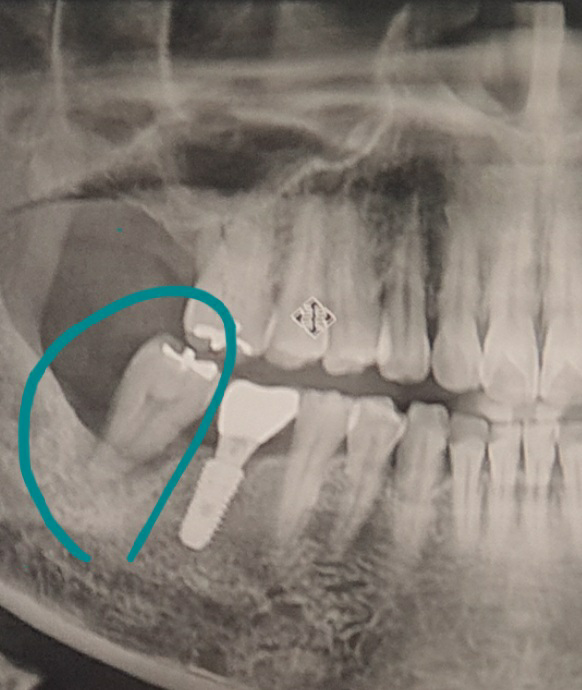

1. 뽑은 치아부분을 임플란트 하시면 되나 파노라마 사진으로 정확히 판단은 어렵지만 앞쪽 치아와 교합되는 부분이 많지 않다면 임플란트를 꼭 하지 않아도 됩니다.

2. 이는 비어 있어서 교합이 되는지 안되는지에 따라 다를 수 있어 보입니다.

3. 만약에 서로 교합되는 부분이 전혀 없다면 비워둔 채로 생활하더라도 저작이나 생활에 큰 불편감이 없습니다.

1. 아래치아 임플란트만 권장합니다.

2. 위치아는 저작기능에 큰 영향을 미치지 않습니다.

3. 아래 치아가 없게되면 위치아가 내려옵니다.

저작 기능에도 영향을 미칩니다.

오랜시간 빈공간으로 방치할 경우 치조골이 소실되어 임플란트를 식립 할 공간이 부족하면 골 이식을 할수도 있습니다.

-일반적으로 가장뒤에 치아가 위아래 없으면 안해도 되는데 환자분은 아래쪽 최후방치아가 위 치아랑 교합이 되는상태라서 알쪽은 임플란트를 하셔야될것같습니다.

아래치아를 빼고나서 가능하면 위아래 1개씩 다 임플란트를 하는게 좋습니다.

물론 치아 한개씩 없다고 해서 저작이 안되는것은 아니지만 어금니가 1개일때보다는 2개일때 더 저작효율이 증가하고, 치아에 부하가 적게 걸리기 때문입니다